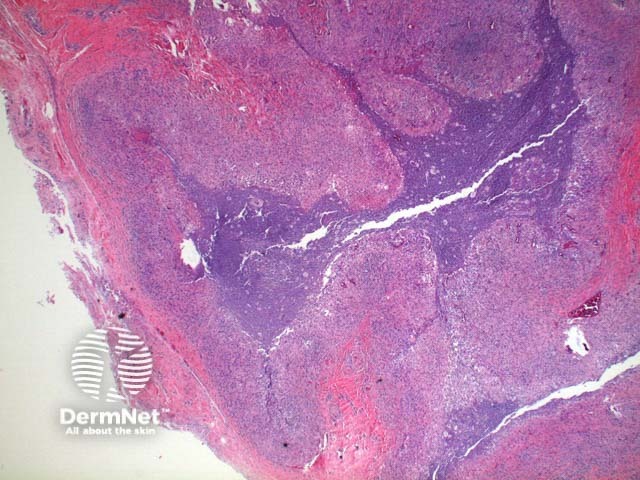

Scanning power view of phaeohyphomycosis shows a deeply extending granulomatous pattern (Figure 1) which may show areas of necrosis (Figure 2). Centrally an abscess or cystic nodule may form. Frequently a foreign body such as a wood splinter can be seen. The epidermis commonly shows pseudoepitheliomatous hyperplasia. The inflammatory infiltrate is comprised of histiocytes with multinucleated giant cells, and numerous neutrophils (Figures 3,4 and 5). At high power branching septate pigmented fungal hyphae can be seen (Figure 6).

Figure 1